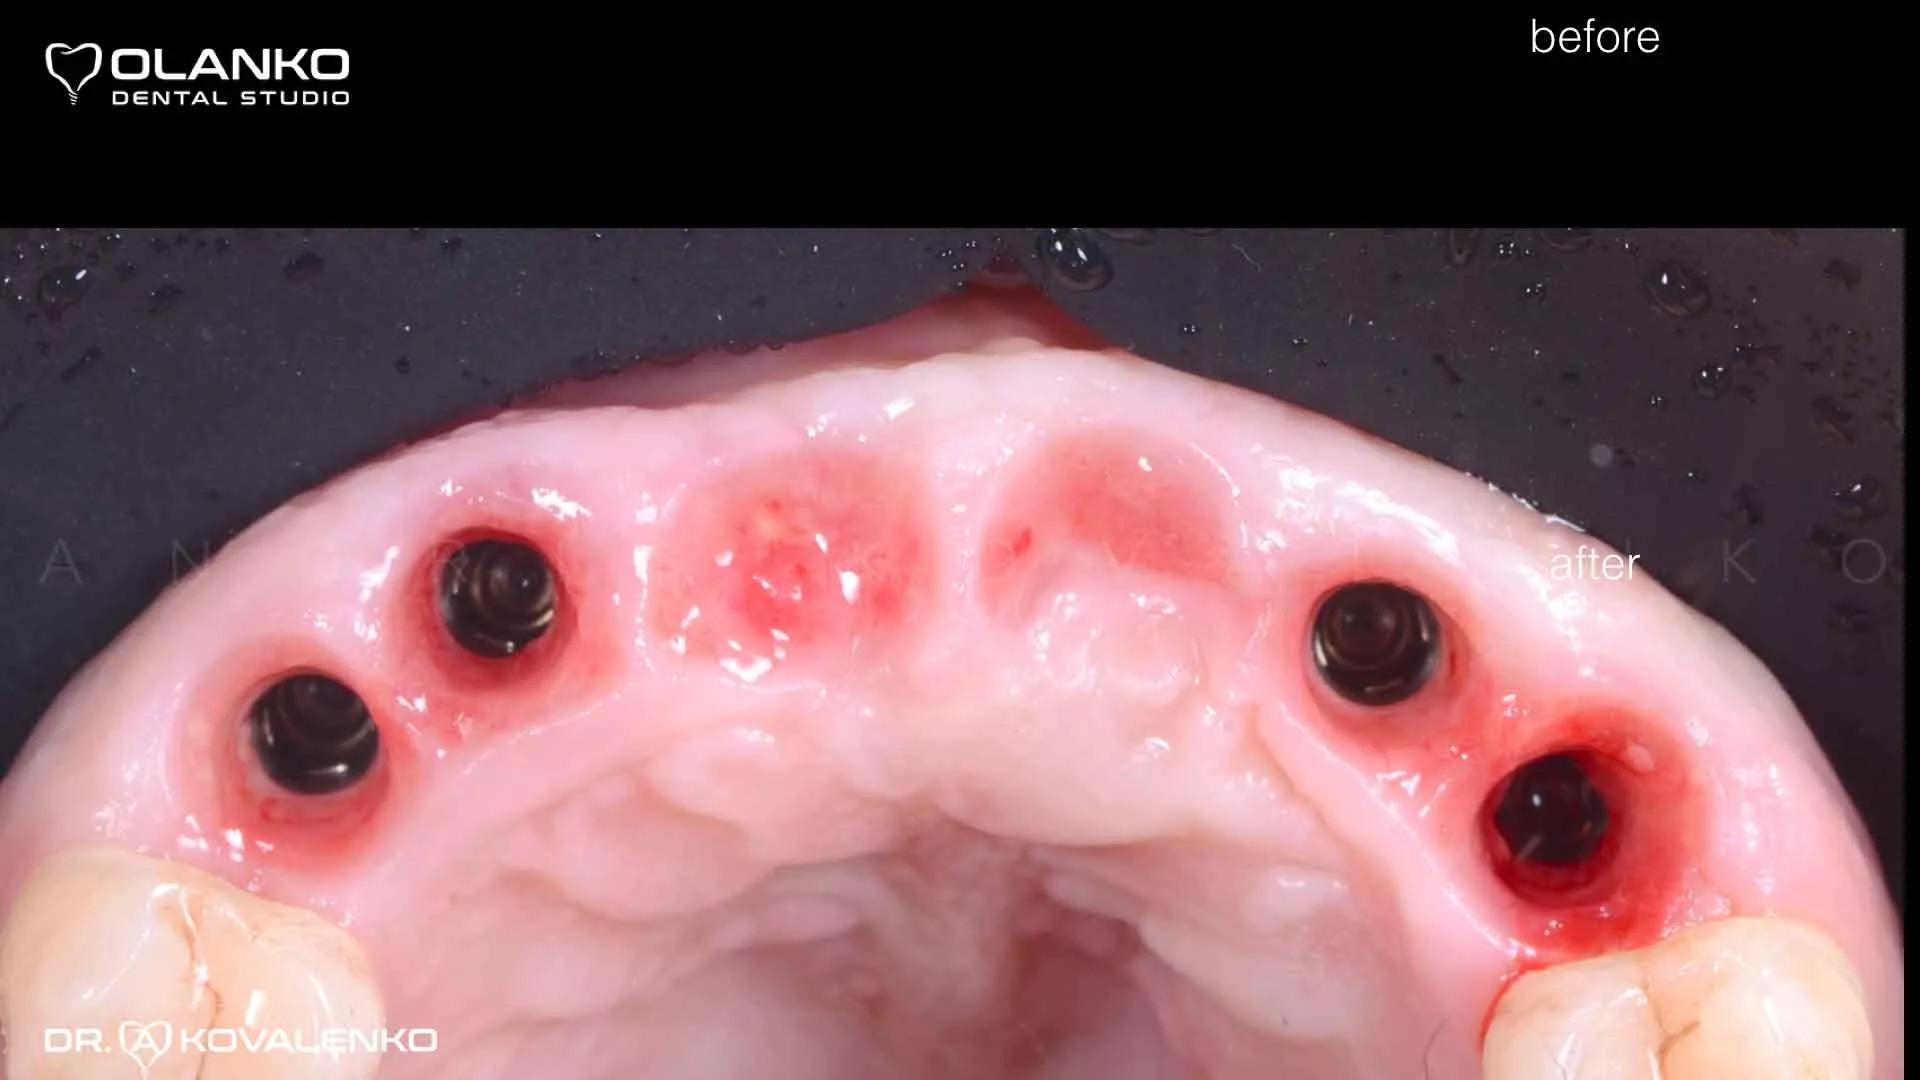

Фото вид ясен навколо імплантатів після приживлення